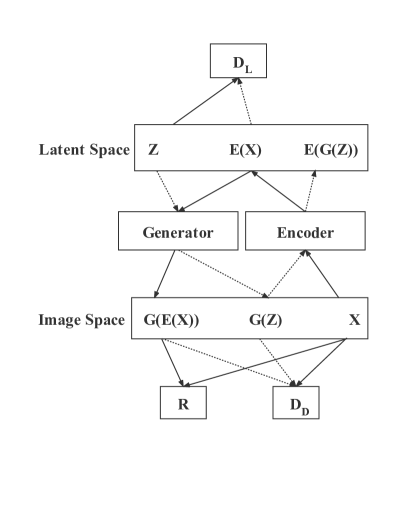

Kwon et al. proposed -GAN-GP that consists of a generator, an encoder, a discriminator, and an additional discriminator L [28], combining VAE and GAN to map random noises to a gliomas MRI distribution successfully. The special structure of -GAN-GP is shown as Figure 2 [28]. VAE attempts to compress discrete pixels in the real training image into a low dimensional continuous space and then reconstruct it back to the original space through encoding [28]. KL divergence is introduced in the encoder and decoder to measure the difference between the distribution of latent variables and the Gaussian unit distribution, forcing the generated image distribution to approach the real image distribution continuously [28]. However, the farther away the generated image by VAE is from the center point, the more blurred it is. Furthermore, the generated image by VAE lacks a detailed description, and it is not easy to generate high-quality images with precise details. Therefore, the combination idea of original -GAN is: (i) although the VAE will generate blurry images, it can avoid the mode collapse problem since all real samples will be encouraged to be reconstructed by an autoencoder; (ii) GAN does not need further constraints on the model, generating more detailed and sharper images than VAE, but GAN will suffer from mode collapse [28]. However, although -GAN can overcome the image blurriness and mode collapse, it is still difficult to train since when the real data distribution and the generated data distribution do not have overlapping areas or can ignore overlapping areas, the JS divergence is usually a constant, which will cause the generator gradient to disappear [29]. Furthermore, the gradient exploding or vanishing may still occur. Therefore, Kwon et al. [13] exploited the gradient penalty (GP) to constraint the training process of -GAN, called -GAN-GP.

-GAN-GP There are four networks: encoder, generator, discriminator, and discriminator L to be trained. For the encoder, the input of the encoder is real data x, and then it will output a latent vector , which will input to the discriminator L. The purpose of the encoder is to deceive the discriminator L into treating the as real. For the generator, the inputs of the generator are random noise and , and then it will output the generated image and the reconstructed image from the two vectors. The generator aims to fool the discriminator to treat the two output images as real and reduce the difference between the real image and the reconstructed image [6]. For the discriminator, the inputs are real images, generated images, and reconstructed images. The discriminator aims to classify these images, treating the generated images and the reconstructed images as fake [6]. The inputs of discriminator L are and . The purpose of the discriminator L is to classify the two classes of vectors, treating the as real, so that the distribution can be as close as possible to normal distribution. The total loss is below:

Where denotes the discriminator of the data space; represents the discriminator of the latent space; E is the encoder; G denotes the generator. The discriminator loss of contains the sum of two distance metrics since the discriminator treats the reconstructed images and randomly generated images as fake [13]. The generator loss uses the L1 distance between the reconstructed images and real images as the reconstruction term. The encoder loss has an identical generator loss form of WGAN-GP. Similarly, the discriminator loss has the identical discriminator loss form of WGAN-GP except for the input, where the input is a latent variable or instead of images. The gradient penalty [31] terms and are added to and . The gradient penalty in discriminator is described as , where is any point sampled between real and generated samples. For the parameters and , they use the fixed value of 10 [13]. In discriminator L, the gradient penalty is described as , where is any point sampled between encoding and random noise samples.